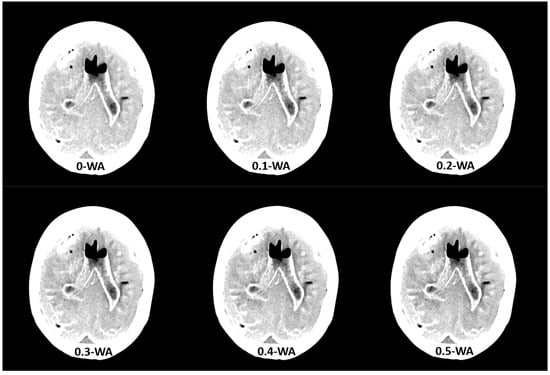

The phantom was scanned with the standard DECT non-contrast head protocol which is used in our hospital on the dual source Siemens Definition Flash scanner. Acquisition is performed at 80 kVp and Sn 140 kVp, where Sn indicates tin filtration of the high- energy tube, with automatic tube current modulation (Care Dose 4d), a pitch of 0.7, and a rotation time of 0.5 s, with XCare on. Quality reference mAs values were 310 for tube A at 80 kV and 155 for tube B at Sn140 kV. The detector configuration was 40 × 0.6 mm. WA reconstructions were generated with WFs from 0 to 1, in 0.1 increments (Figure 2), using the Siemens iterative reconstruction algorithm (SAFIRE) at level 3. The axial soft tissue and bone reconstructions were sent to the Picture Archiving and Communication System (PACS) and to a dedicated workstation.

Figure 2.

Weighted average (WA) image datasets with different weighting factors (0 to 1) on an anthropomorphic phantom at the level of basal ganglia with the scout image. All images are displayed using the same window width and window level (WW 80, WL 35).

GM–WM CNR and noise generally increased when WF values increased from 0 to 1 (Figure 6). The 0.9-WA reconstructions had the highest CNR, and 0-WA and 0.1-WA had the lowest. SCA and PFAI were lowest for 0-WA images and highest for 1-WA images. Qualitative analysis showed unacceptable GM–WM contrast on 0-WA, 0.1-WA, and 0.2-WA image datasets for two readers. All readers rated GM–WM contrast as very good or excellent at 0.5-WA, 0.6-WA, and 0.7-WA. No or minimal posterior fossa and subcalvarial artifacts were noted at 0-WA, 0.1-WA, 0.2-WA, 0.3-WA, and 0.4-WA, while 0.9-WA and 1-WA reconstructions were considered unacceptable or for very limited evaluation by all readers. The overall IQ was rated as very good or excellent by at least two readers for the 0.5-WA, 0.6-WA, 0.7-WA, and 0.8-WA image datasets. The interrater consistency results for the assessment of the different IQ metrics for all 11 image datasets are presented in Table 2. The agreement for SCA assessment was moderate, while the interrater agreement for noise, GM–WM contrast, PFA, and overall IQ was good.